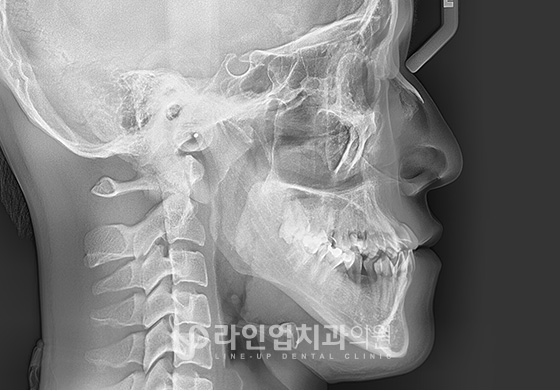

Өмнө болон дараах зураг

Before

After